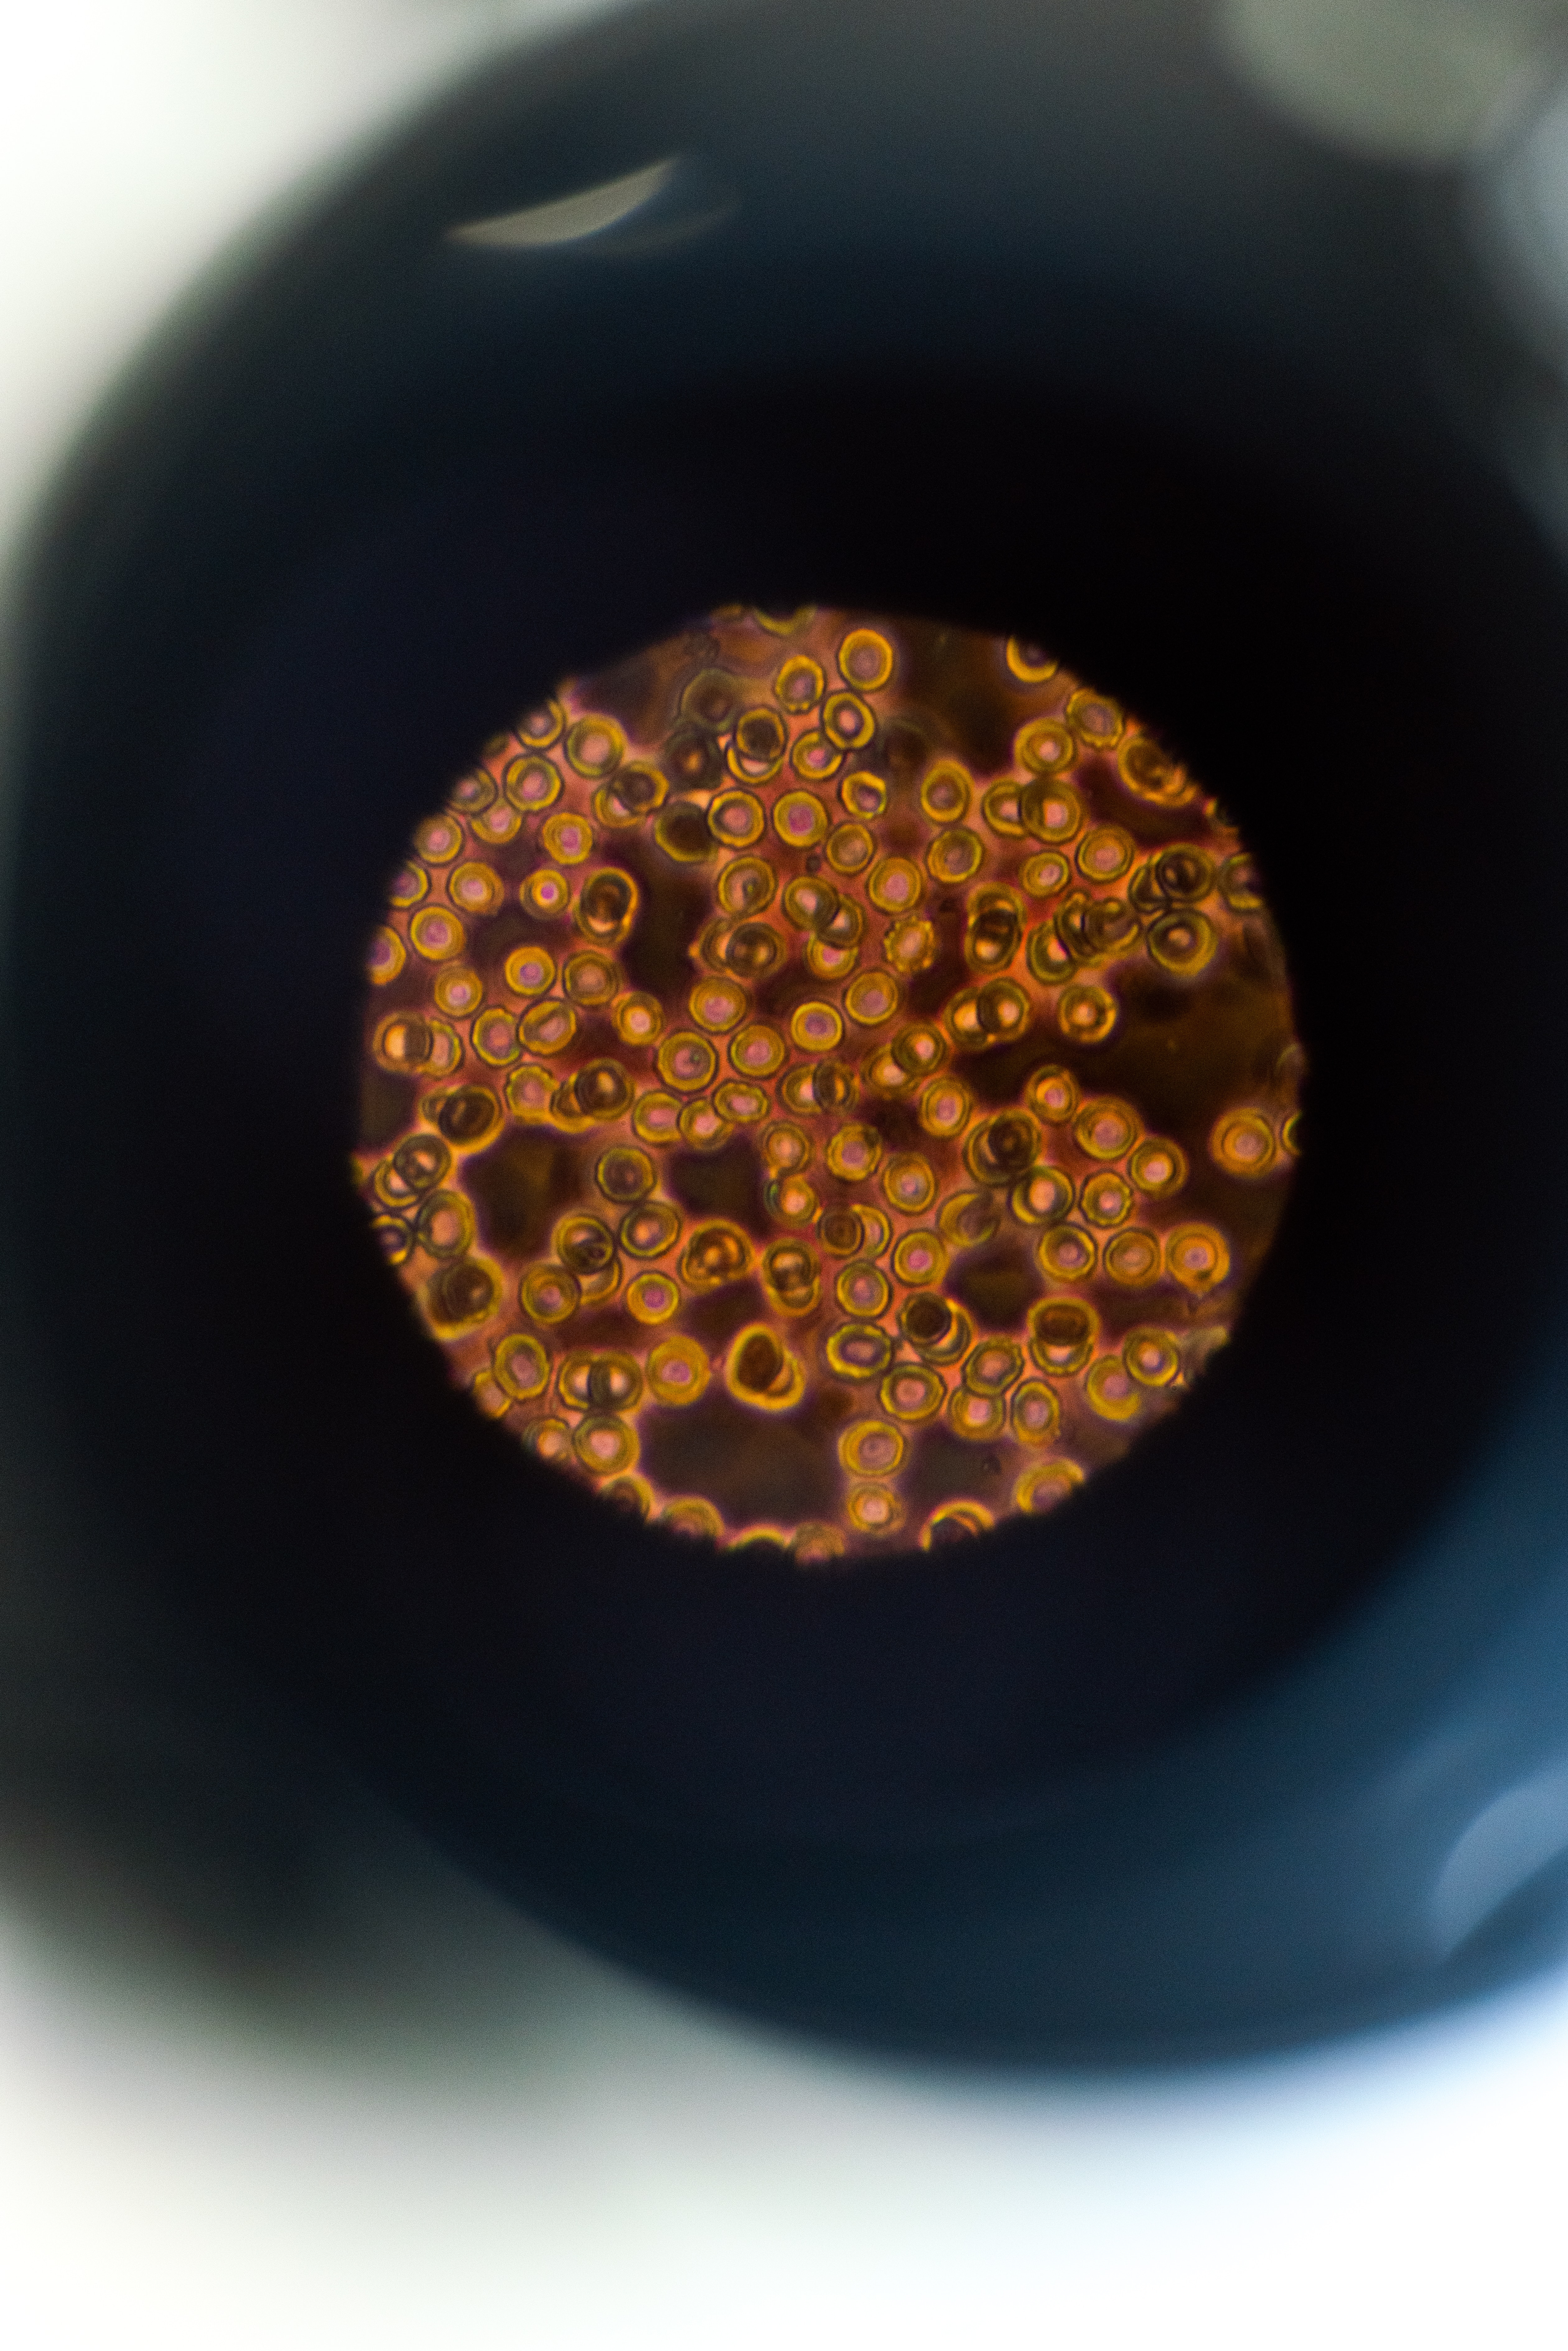

Kanser, bazı etkilerle değişime uğramış hücrelerin, gerek yerel ve gerek uzak noktalarda kontrolsüz olarak çoğalıp büyümelerinin sonucu oluşan hastalıklar grubudur.

Moleküler biyolojinin verdiği yeni bilgiler kanser tedavisi için umut vaad etmektedir. Kanserli hücrelerinin çoğalmasını tetkleyen genleri ve onların ürünlerini baskılayan özel maddeler halen araştırılmaktadır. Aynı zamanda kanser genlerini baskılayan genlerin de tedaviye katılmaları için çalışılmaktadır.